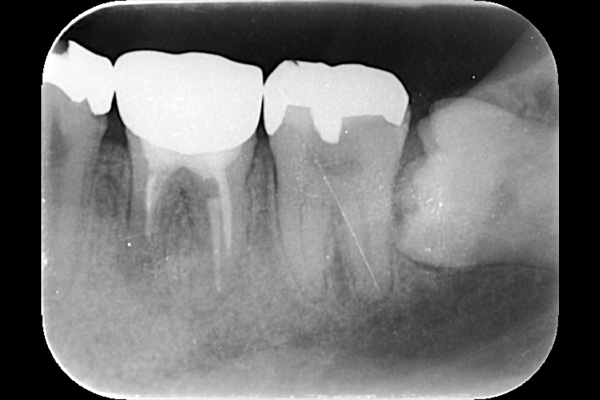

| 根の中の薬が十分に充填されておらず、根の先が周りと比べて黒くなっており、炎症があると判断できます。 | 根の中にしっかりとお薬を緊密に充填しましたが、まだ根の先に黒くなっている部分があります。 |

それは歯の先に枝分かれが多く存在し、そこにばい菌が入り込んで難治性となっているからです。ではその場合どうするのか?外科治療をします。その枝分かれの部分を切り落とすのです。今回はその前後のレントゲンの写真をお見せします。